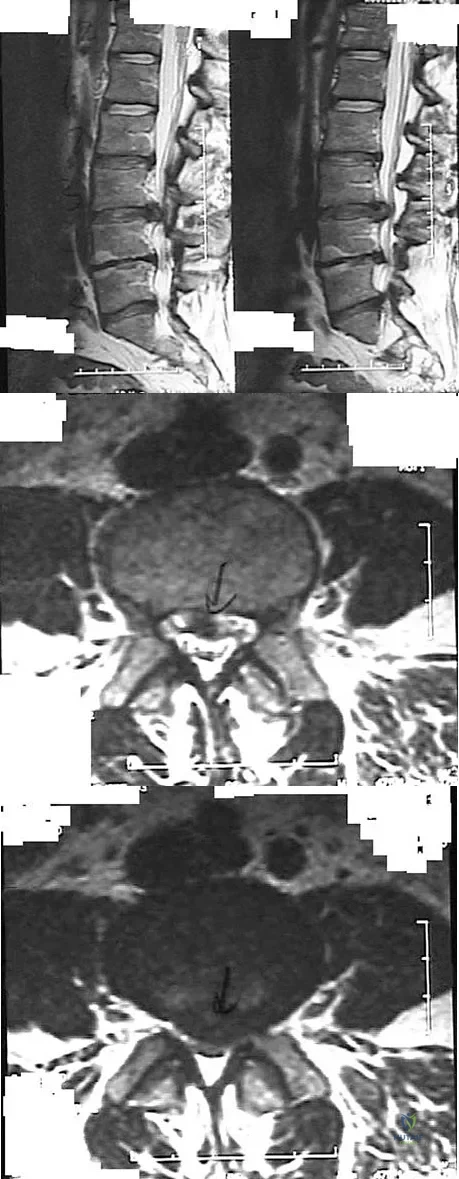

A 19-year-old woman reports lower back pain following a motor vehicle accident. Radiographs obtained immediately after the accident and a bone scan obtained 4 weeks later are shown in Figures 25a through 25c. The patient asks questions regarding the cause, genetics, and natural history of her condition. She should be informed that the condition was

Explanation